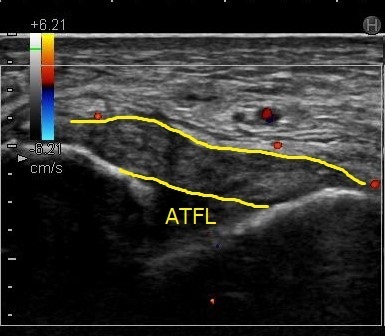

超音波検査

例)

ATFL(前距腓靱帯)損傷

前距腓靱帯が黒く腫れていて、靱帯の線維構造がはっきりしません。